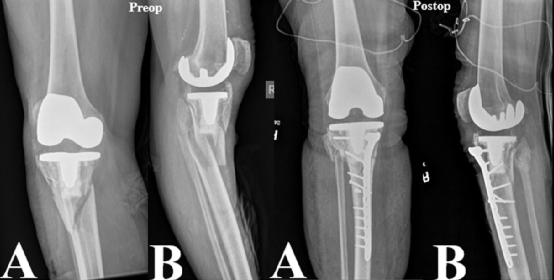

图4. Felix III型骨折术前、术后的正侧位X光片